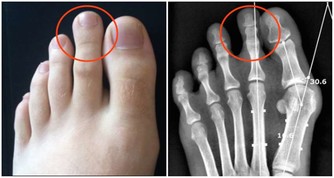

葫蘆素(英語:Cucurbitacin)是從中藥中提取,可治療肝炎及肝癌,存在於深綠色果類或果蒂部位,但誤食過量會有噁心、嘔吐、腹瀉等胃腸道症狀